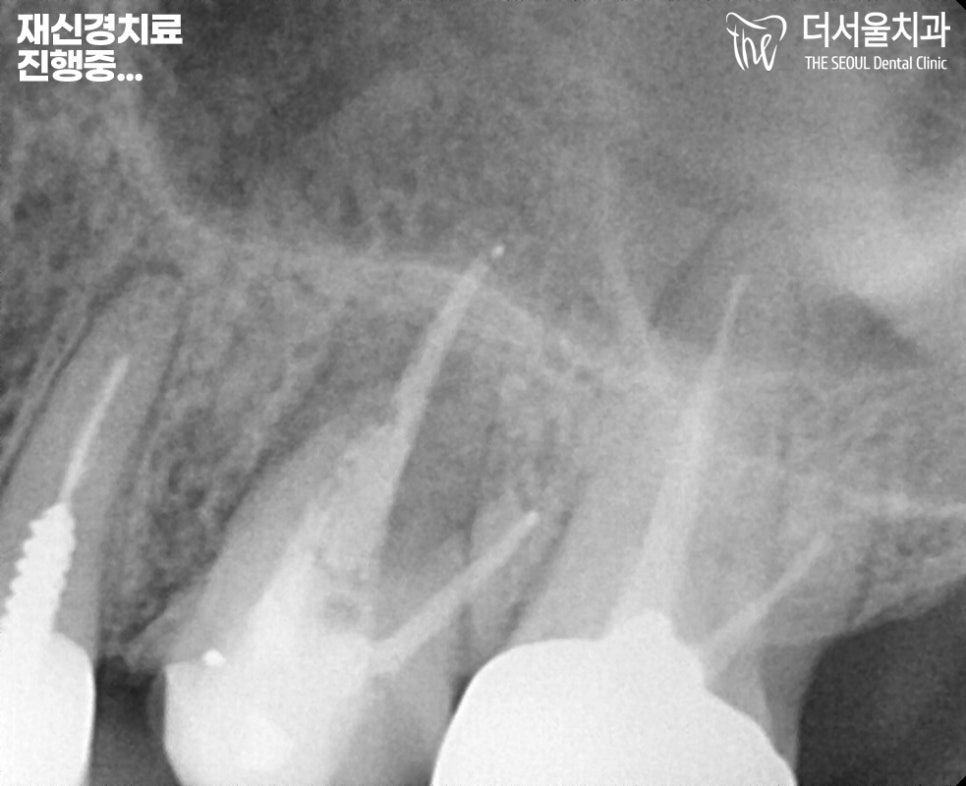

『재신경치료 진행중…

야탑역치과 잘하는곳』

문제 있는 26번 어금니의 크라운을 제거 후,

재신경치료에 들어갔습니다.

이런 경우는 내부를 들여다봤을 때,

되게 지저분하다라는 것을

확인할 수 있는데요.

이것은 내부가 곪았다는 것을 의미합니다.

여러번 균을 제거하고

깨끗하게 소독하는 것을

반복 과정을 거칩니다.

그렇게 해야 또다시 재발하지 않아

재진료를 피할 수 있습니다.